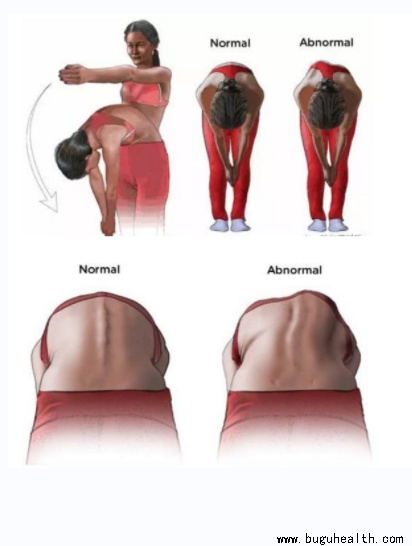

- 布骨医学科普:脊柱侧弯的康复功能锻炼方法! BuGuRMC布骨康复医疗中心 ,2023-06-26

- 脊柱侧弯是非常常见的一个问题,那么,如何简单的判断一个人是否有脊柱侧弯呢?如果你患有背部疼痛或轻度脊柱侧弯,或者你想预防脊柱侧弯,请开始下面的练习。.....